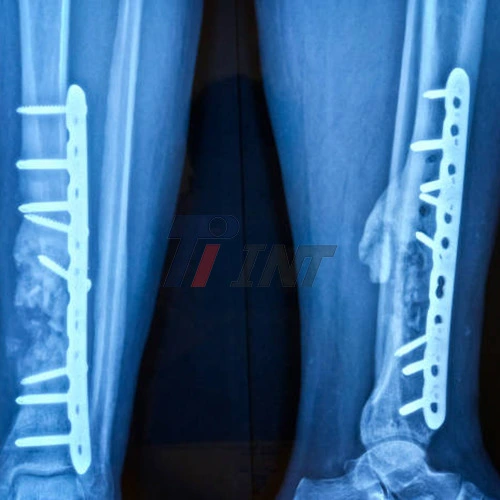

Recovering from surgery involving a titanium plate in leg can be a complex and time-consuming process. Whether you've experienced a severe fracture or undergone a procedure to correct a bone deformity, understanding the recovery timeline is crucial for managing expectations and ensuring proper healing. In this comprehensive guide, we'll explore the various factors that influence recovery time, typical milestones in the healing process, and strategies to optimize your recuperation after receiving a titanium plate in your leg.

When a titanium plate in leg is surgically implanted in your leg, your body quickly starts the complex recuperating process. The to begin with stage, called the fiery arrange, ordinarily keeps going a few days after surgery. During this time, you may encounter swelling, pain, and confined development as your body reacts to the harm. Taking after this, the mending prepare moves into the repair stage, where modern tissue begins to shape around the titanium plate and broken bone. This stage is fundamental for stabilizing the bone and supporting the development of solid tissue to advance long-term recuperation and work.

Typically, patients can anticipate at least 6-8 weeks for starting bone mending, but full recuperation may take a few months to a year. During this period, the bone continuously recaptures quality and usefulness, while the encompassing tissues alter to the nearness of the titanium plate in leg. The mending handle is progressive, with enhancements in portability and quality happening over time as the bone proceeds to repair and the body adjusts to the embed.